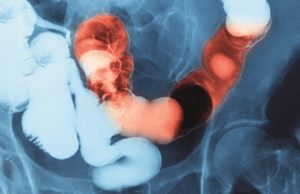

İnflamatuvar bağırsak hastalığı

19 Mayıs Dünya İnflamatuvar Bağırsak Hastalıkları (İBH) Günü’nde hastalığa dikkat çeken Prof. Dr. Metin Başaranoğlu, İBH’nın tedavisinde düzenli doktor kontrolünün önemine vurgu yaptı. Prof....

İlaç bulamayınca, günde 20 kez tuvalete gidiyorlar

İnflamatuvar bağırsak hastalığına (İBH) sahip kişiler, piyasada ilaç bulamamaktan yakınıyor. Karın ağrısı ve kanlı ishal şikayetleri bulunan ve günde 20 kez tuvalete çıkmak zorunda...